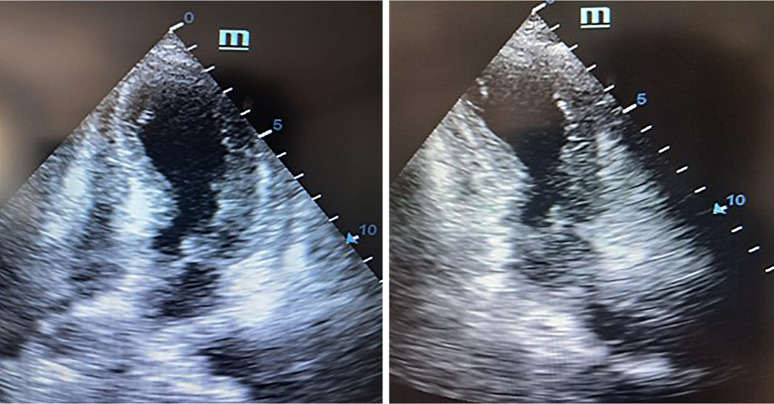

Case presentation: A smoker in their 70s with metastatic lung adenocarcinoma experienced an anaphylactic reaction during the second cycle of atezolizumab. The reaction was accompanied by chest tightness and elevated troponin T levels. Echocardiographic evaluation revealed severe dilatation of the left ventricular apex and a significantly reduced left ventricular ejection fraction. Coronary angiography excluded significant coronary stenosis but confirmed apical ballooning, consistent with the type I variant of KS. This diagnosis underscores the potential for immune-related cardiovascular events associated with ICIs to mimic acute coronary syndromes, challenging clinicians to distinguish between immune-mediated effects and primary cardiac conditions.